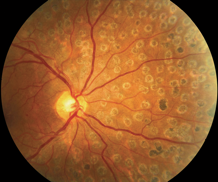

人类眼底的正常形态

人类眼底结构由视盘(也称视乳头)、视网膜和视网膜血管组成。

视盘呈粉红色,边界清晰。

视网膜动脉和静脉由视盘沿着四个象限的方向(即颞上、颞下、鼻上、鼻下)发散,形成许多小分支。正常的视网膜动静脉管径比大约为2:3。

黄斑呈椭圆形,是靠近视网膜中心的色素区域。它的颜色较深,直径约5.5毫米。黄斑中心为中央凹。